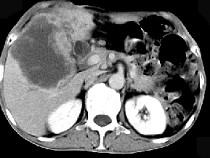

问题 男,49岁,右上腹痛半年,轻度黄疸,AFP阴性,CT检查如图,最可能的诊断为()

选项 A.原发性肝癌 B.胆管细胞癌 C.局灶性脂肪肝 D.肝脓肿 E.肝淋巴管瘤

答案 B